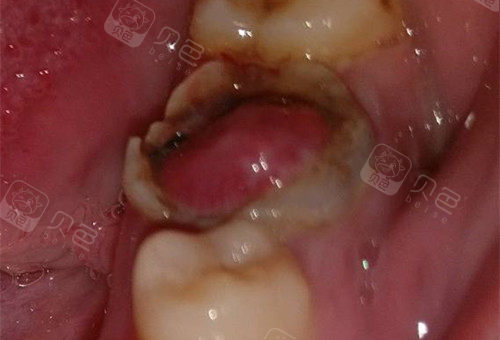

智齿牙髓息肉 - 口腔专业讨论版 -丁香园论坛

牙齿龋坏 息肉